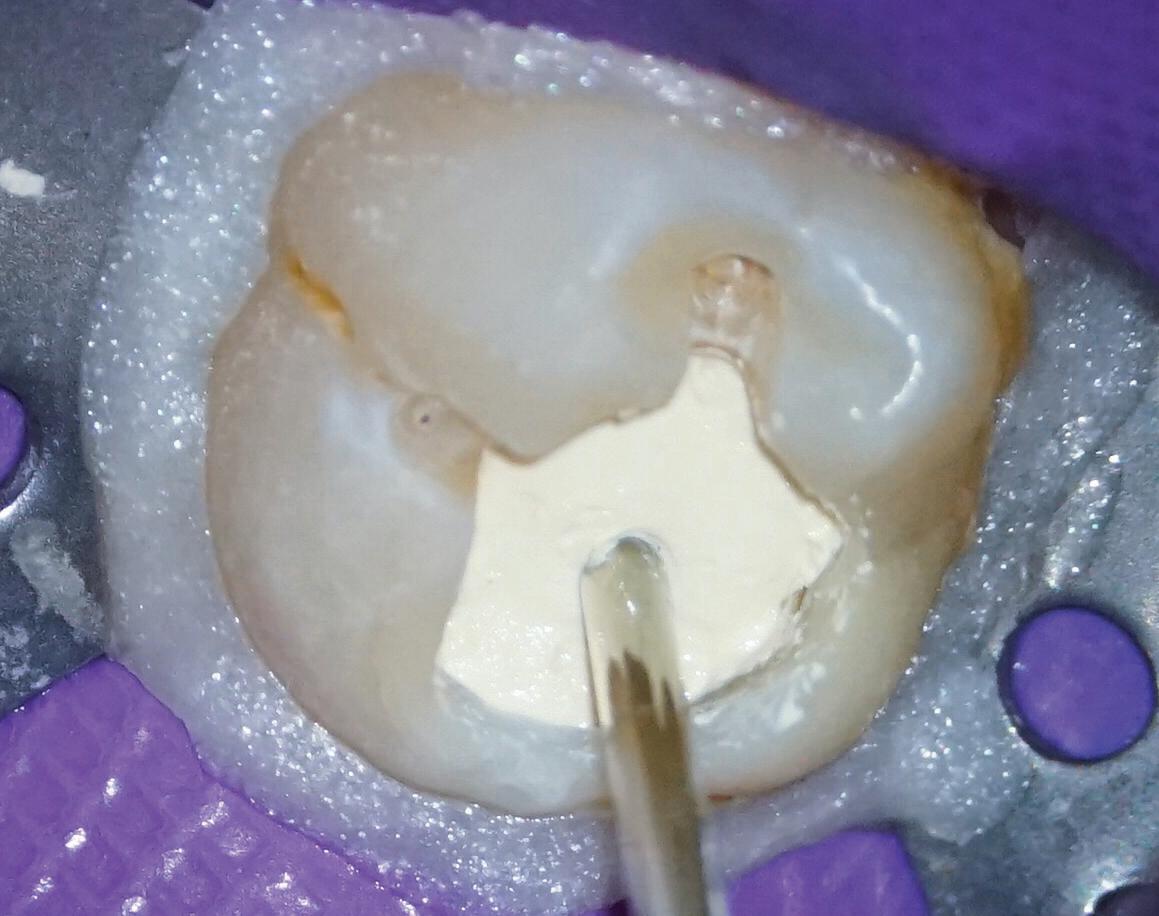

Estelite Asteria (Tokuyama)One of my favourite composite resin materials is Asteria which is a light-cured radiopaque composite for universal use. It considerably simplifies multilayer techniques yet delivers outstanding aesthetics with excellent polishability. Unlike mul tilayer techniques used with conventional composites, Asteria uses only 2 layers for optimal results without compromising aesthetics. The microstructure of the material produces a light diffusion that helps blend in with the natural tooth structure. The chameleon like nature of the material allows a blending of the materials to natural tooth structure and it allows excellent polishability which retains its lustre over time.